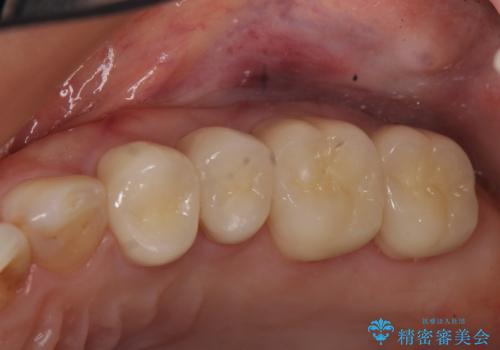

- 左上の奥歯を綺麗にしたいといらっしゃった方の症例です。

左上4、5、6、7番目の歯をオールセラミッククラウンにより補綴しました。

今回用いたオールセラミッククラウンは、ジルコニアフレームという白い素材の上にセラミックを盛っているため審美性が非常に高いのが特徴です。

またジルコニアは人工ダイヤモンドの材料にも使われているほど高い強度を持っており、そのためオールセラミッククラウンは審美性だけでなく、奥歯やブリッジの補綴も可能とするクラウンです。